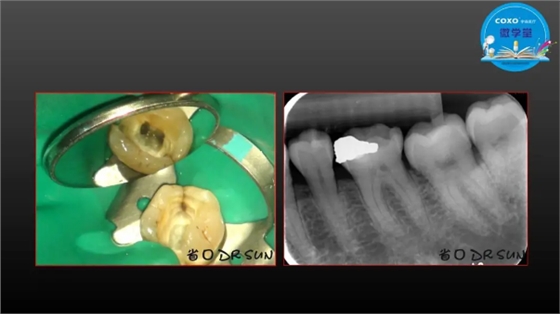

主任医师,牙体牙髓副主任, 广东省口腔医院牙体牙髓科 主任医师。2003年硕士研究生毕业,研究方向为牙体牙髓病学,擅长于牙体牙髓病的诊断、龋齿、牙髓炎、根尖周病的治疗以及前牙美容修复。